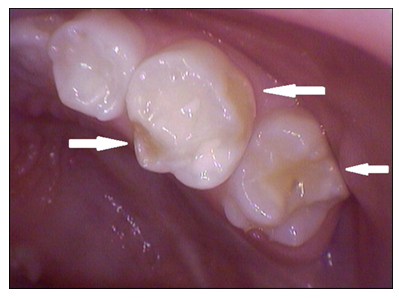

Razvojni defekti se razvijaju i na bočnim zubim i ponekad je i za stručnjaka teško da ih primeti.(slika 6.). Na ovakve defekte se često nadovezuje karijes. Slična pojava je karakterističnija za stalne zube i zahvata sekutiće i prve kutnjake(“šestice”) i naziva se MIH(Molarno sekutćna hipomineralizacija).